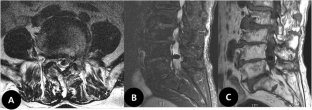

Increased size of a gas-filled intradural cyst causing acute foot drop: a case report

We describe the case of a 76-year-old man presenting with a gas-filled intradural cyst that increased in size over a 10-month period and caused acute bilateral foot drop. The gas-filled intradural cyst was resected from the adherent cauda equina, and histopathological examination identified cystic tissue with degenerated fibrocartilage. Leg pain disappeared immediately following surgery, and the bilateral foot drop resolved within 8 months.

Fig. 1